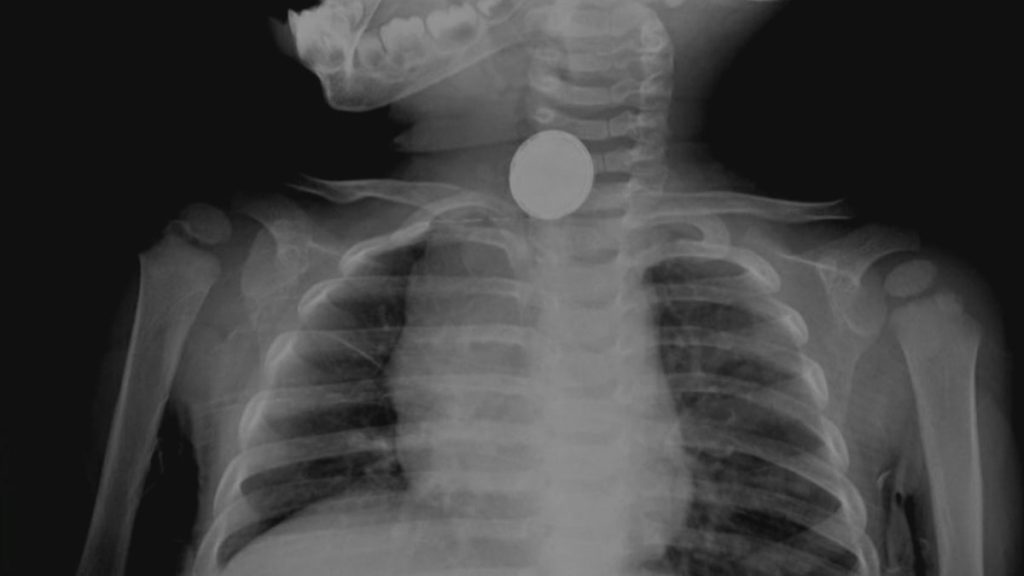

Siegel said he once treated a 10-year-old patient who had a clogged nasal passage that was causing the child a lot of pain.

“It took me a while to figure out that he had stuck a battery up there,” he said.

“Luckily, it didn’t leak,” he added — “and we were able to get it out.”